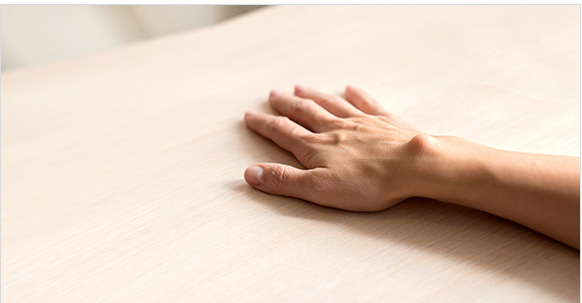

검사 / 진단

외관상으로 혹의 위치나 크기 등을 직접 보고 진단하는 경우가 있습니다. 다른 질환의 유무나 결절종의 잠재성이 있는지 진단하기 위해 초음파 검사나 MRI 검사를 받기도 합니다.

결절종 진단